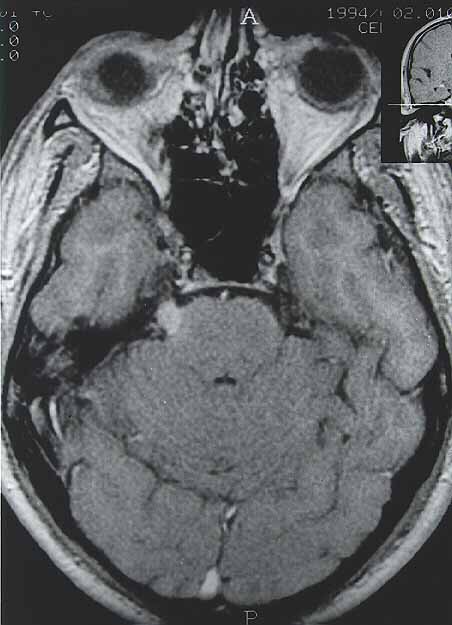

Fig. 3. Imagen axial con las mismas características que las de la Fig. 1.

Fig. 1. Imagen coronal de MRI con contraste ponderada en T1 en la que se observa una captación nodular del trigémino derecho en su zona de salida de la protuberancia, sugestiva de schwannoma trigeminal.